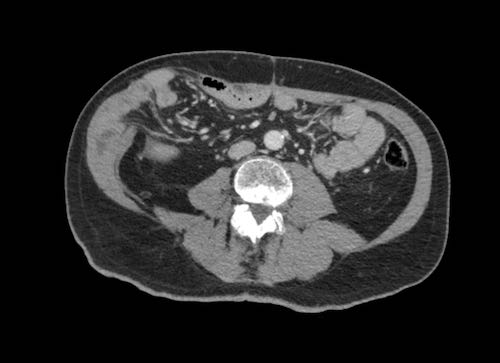

Có một lượng nhỏ dịch cổ trướng.

Mạc treo ruột dày được quan sát thấy bám vào đoạn cuối của ruột non, hình ảnh điển hình của tổn thương xâm lấn mạc treo.

Hình ảnh này thuộc về một bệnh nhân khác nhập viện với cổ trướng.

Hình ảnh

Mạc treo ruột dày (dấu hoa thị) được quan sát thấy bám vào đoạn cuối của ruột non.

Đây là hình ảnh điển hình của tổn thương xâm lấn mạc treo trong ung thư phúc mạc.

Trên CT, hình ảnh dày mạc treo ruột cũng có thể được ghi nhận.